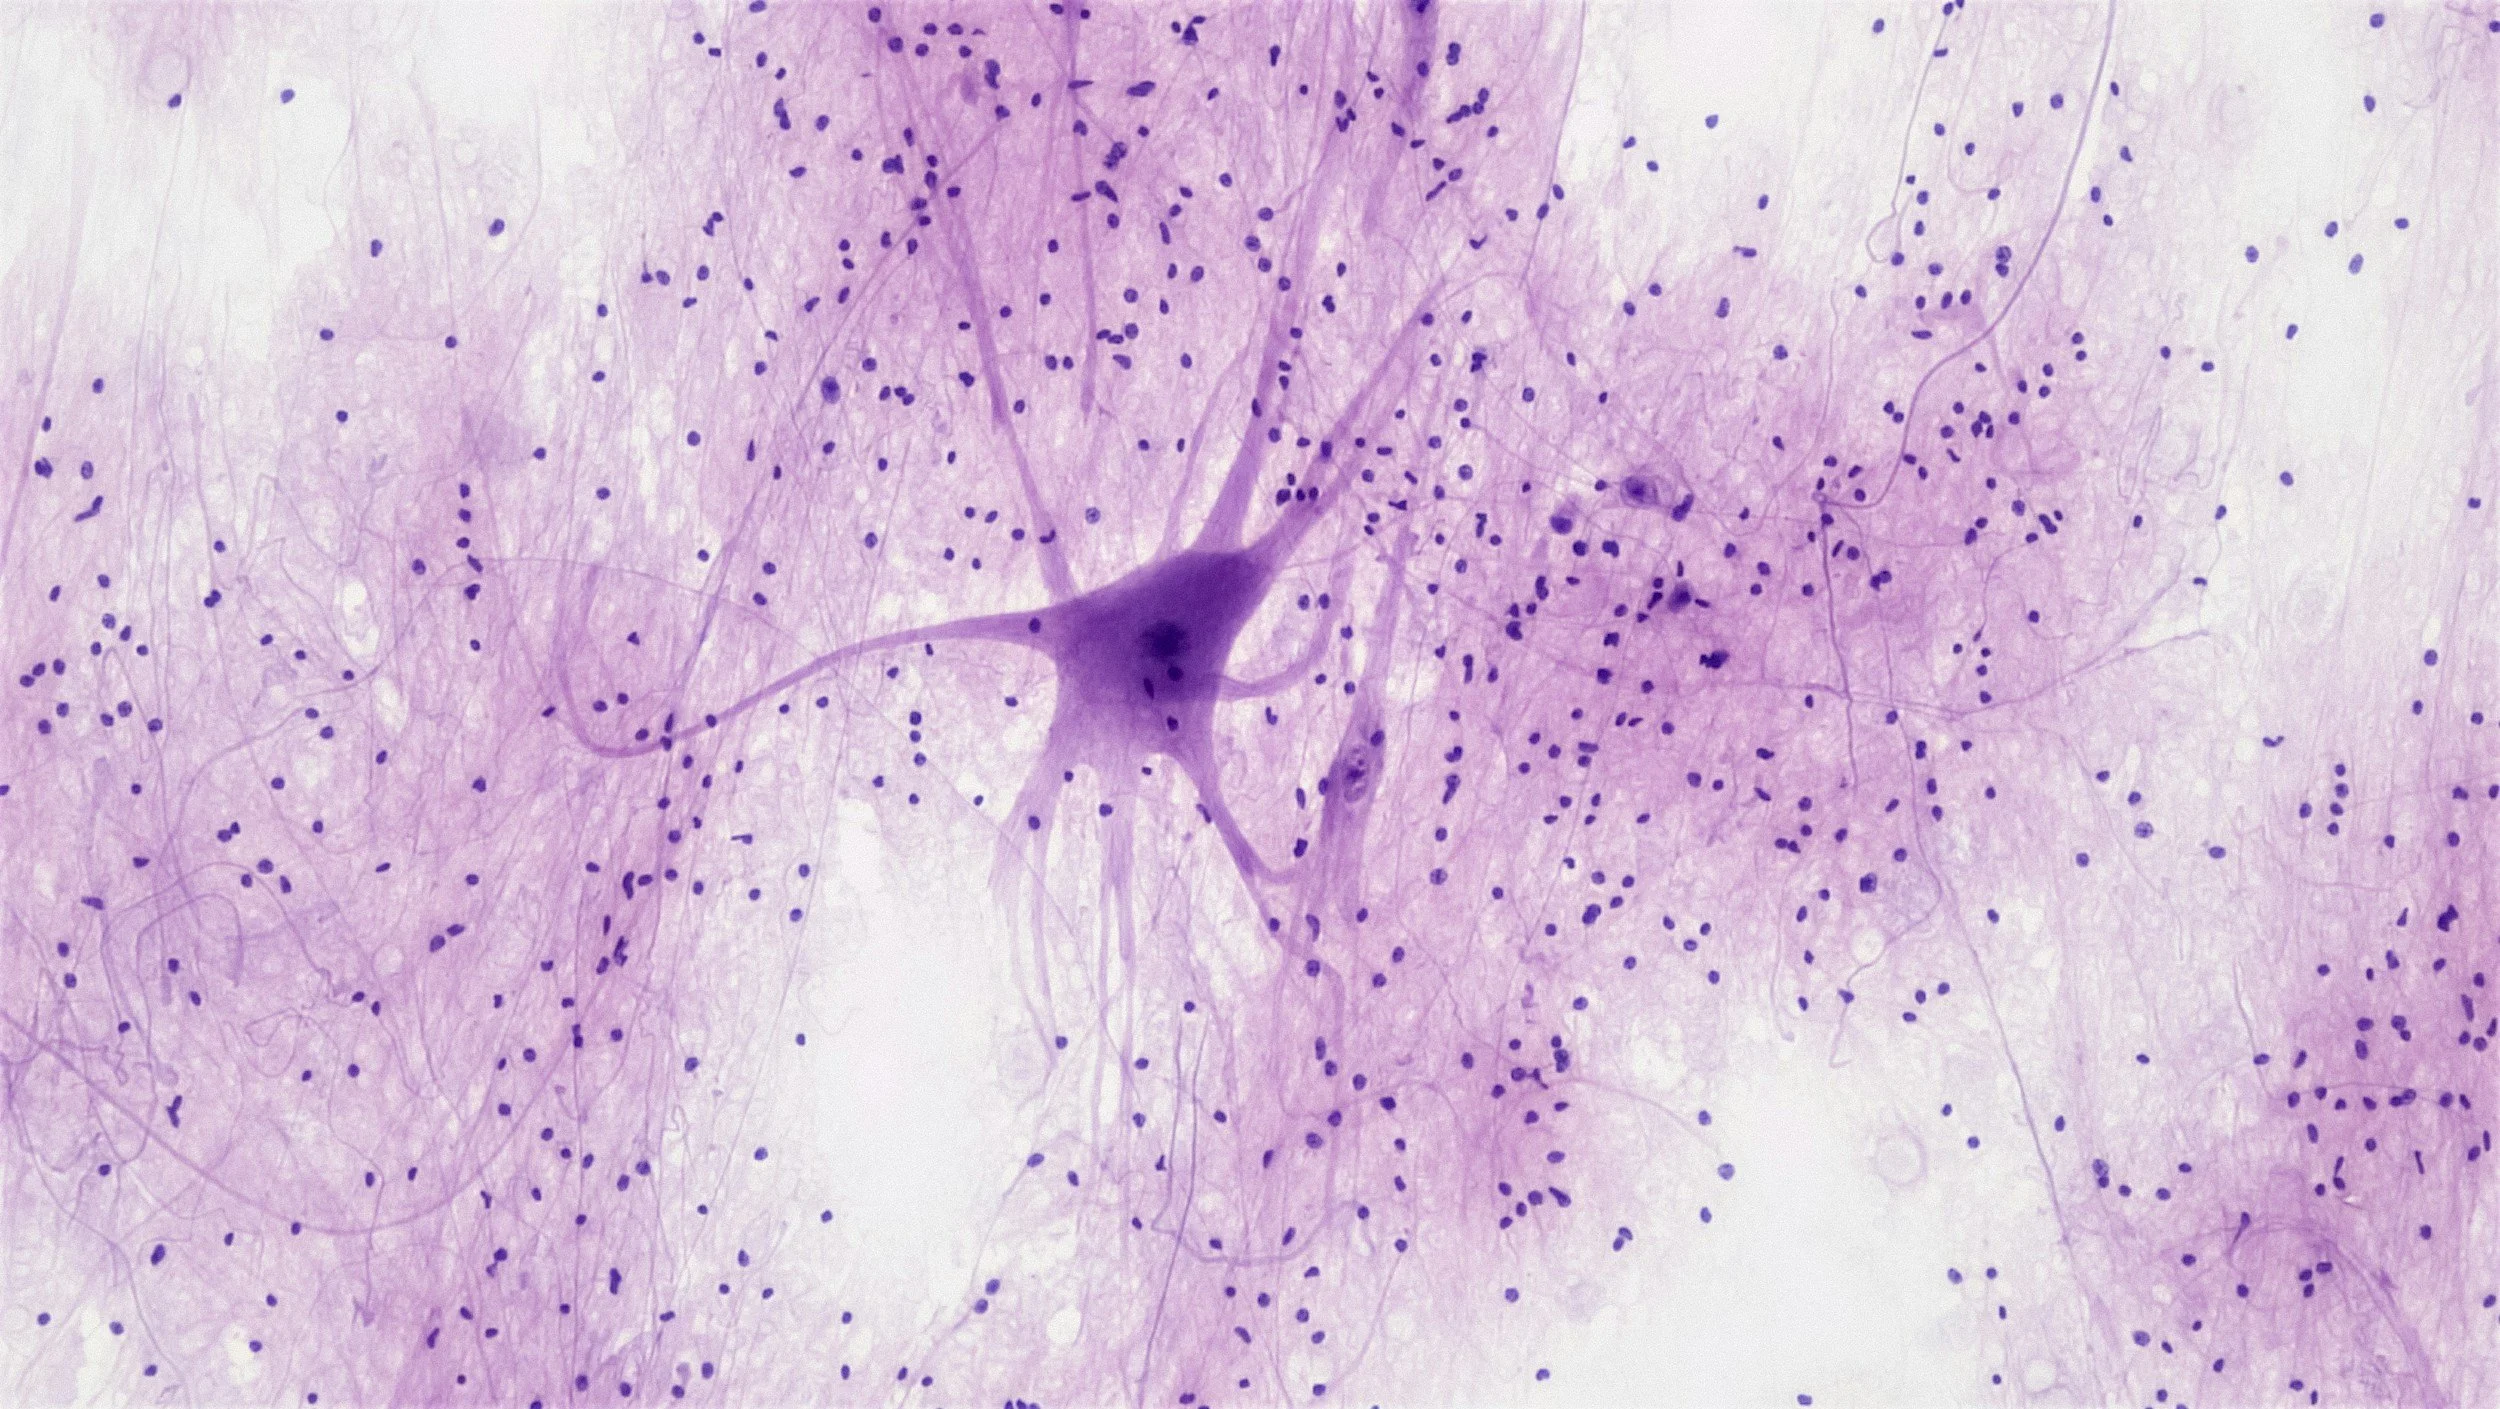

Pioneering discoveries in neuronal cell death, survival, and the molecular mechanisms of neurodegenerative diseases.

The BRAIN Lab brings together seven labs to uncover how brain cells die and survive, driving discoveries in Parkinson’s, Alzheimer’s, and stroke. We pioneered Parthanatos and identified key disease genes, with therapies now advancing toward the clinic.